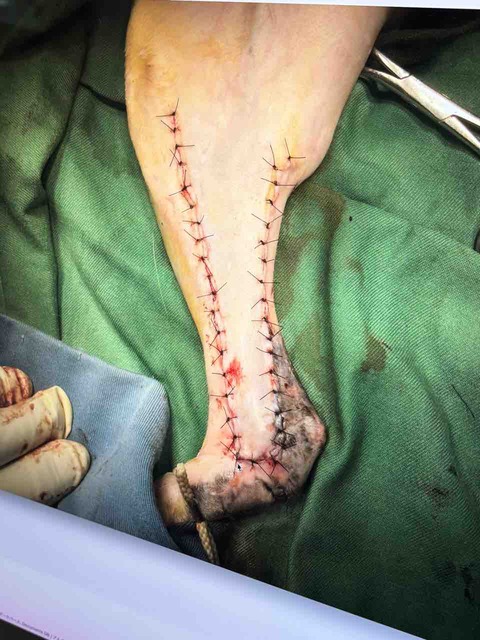

ですが、子猫の保護シーズンの為、次から次へと保護しなければいけない子猫の医療費や(ノミダニ寄生虫の駆除や下痢)怪我した猫などの治療費。